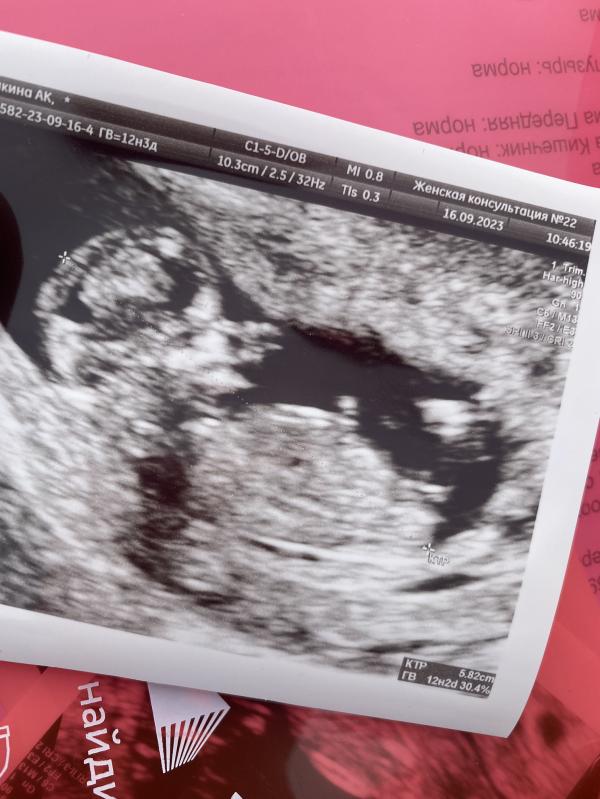

Девочки , сегодня 12.3 был первый скрининг, предположили девочку по половому бугорку , а как вы думаете кто? Если возможно киньте плиз ваши фото узи на этом сроке и пол ребёнка))

О я тоже в жк 22 наблюдаюсь и как раз это узи там делала))

Тоже сказали что будет девочка) я думаю что все таки рано для определения пола